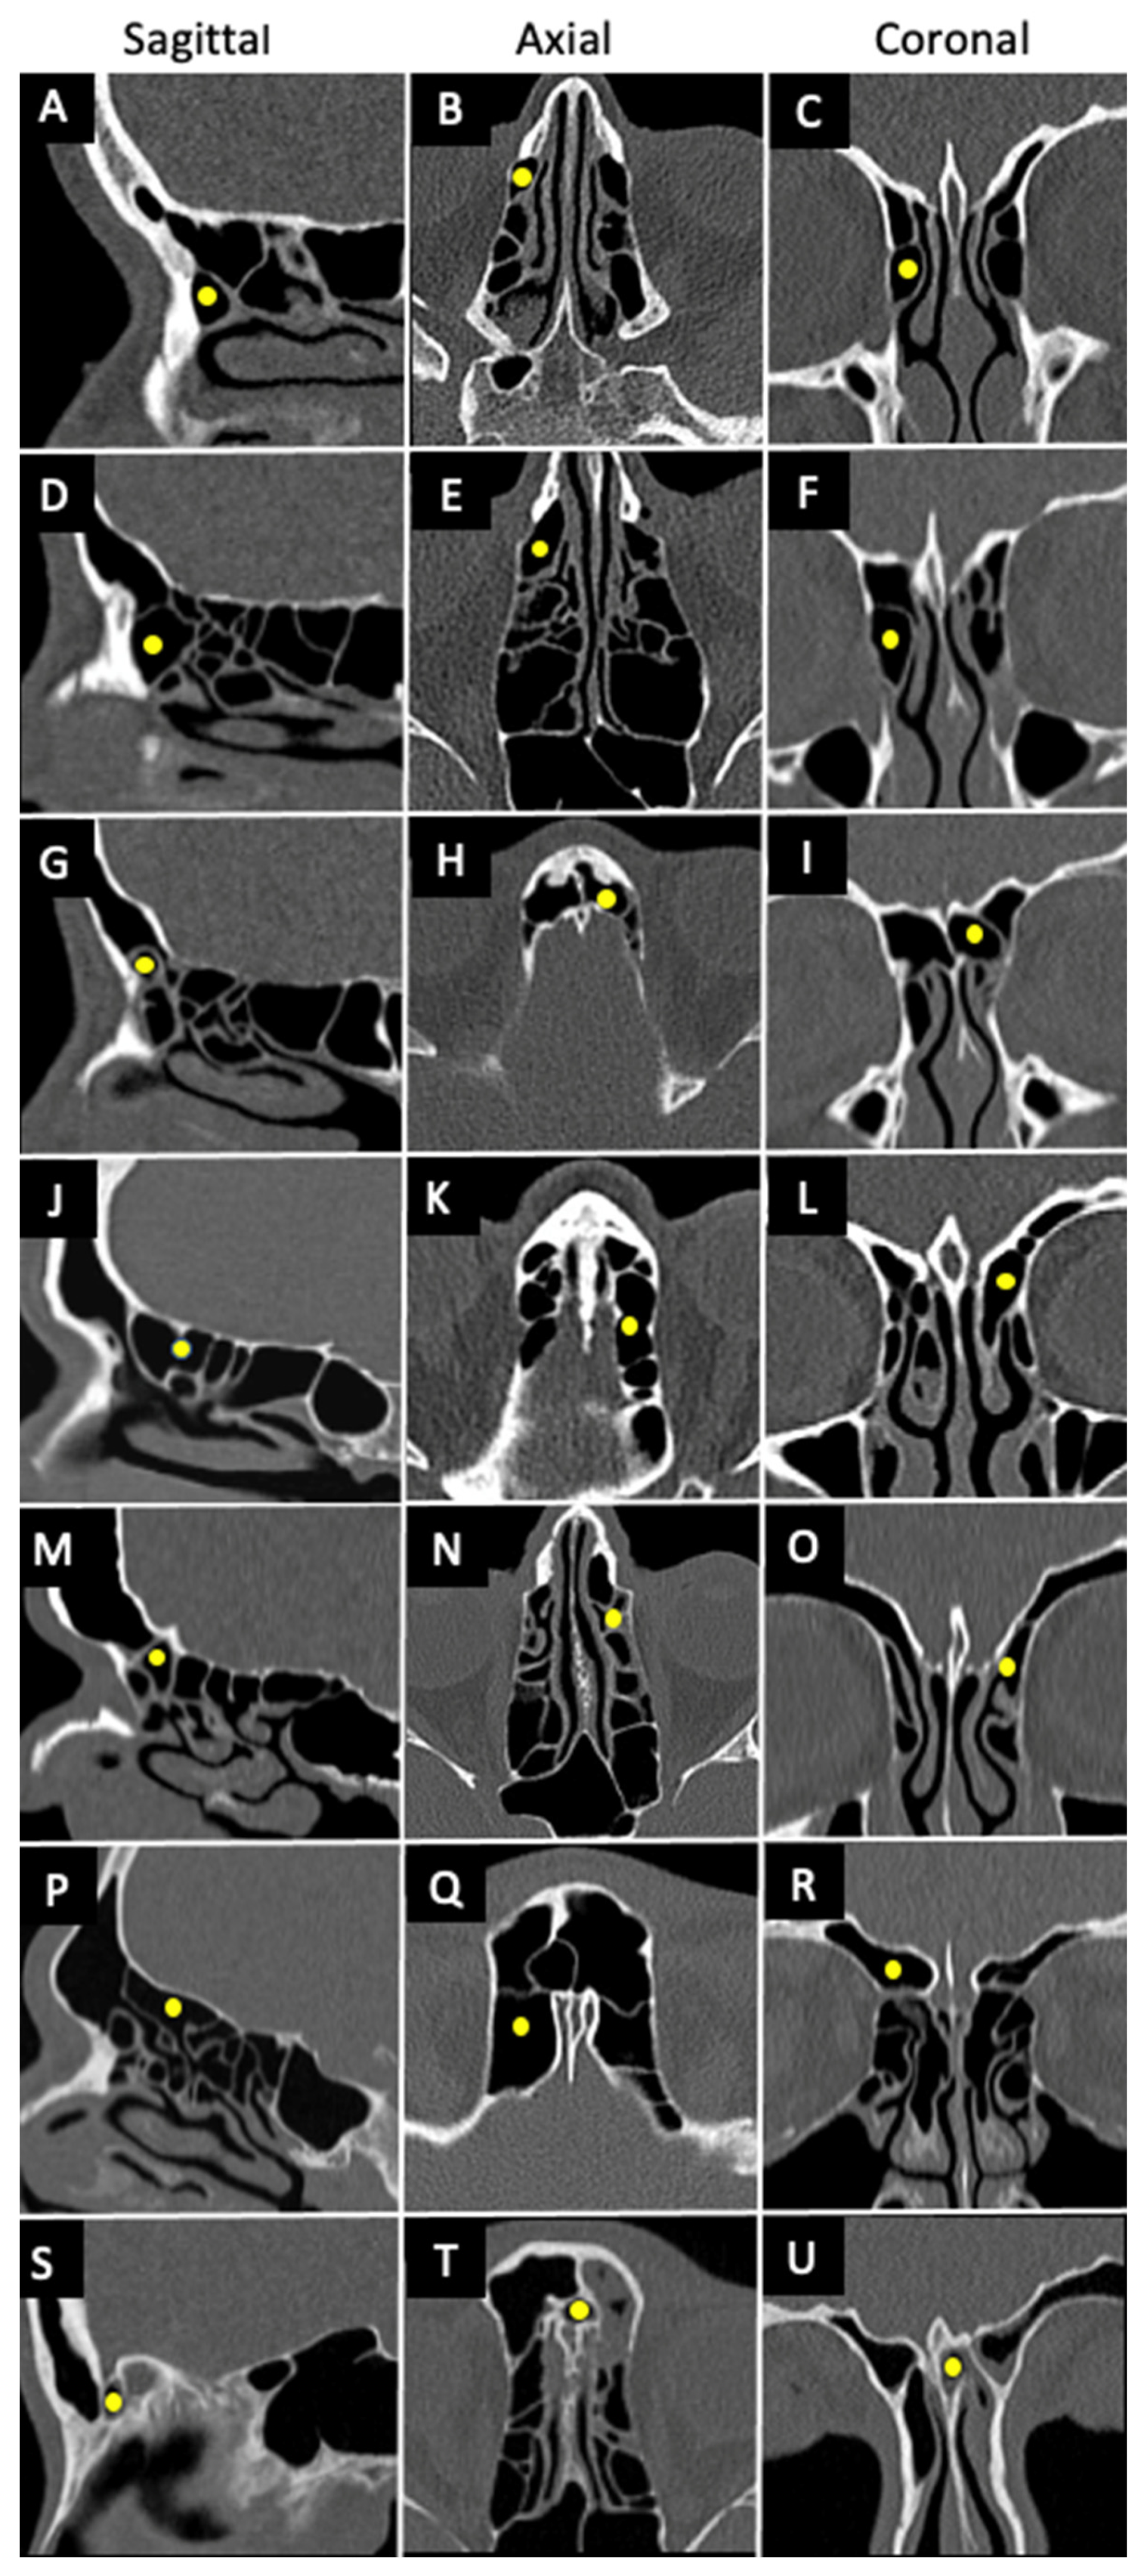

1.3. International Frontal Sinus Anatomy Classification (IFAC)